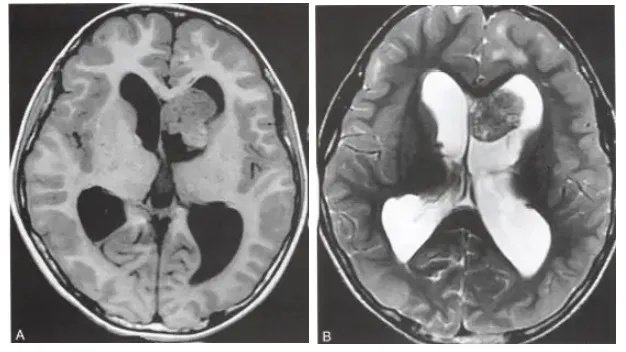

MRI

(1)T1加权相:相对比于灰质,呈等低信号,钙化部分可能呈高信号

(2)T2加权相:混杂等高信号,钙化部分低信号

(3)FLAIR加权相:混杂高信号,急性脑积水和脑脊液渗入继发的室周高信号

(4)T2*/GRE/SWI:钙化部分呈现黑色的磁敏感改变

(5)T1加权增强相:明显强化

(6)DWI:对比于TSC错构瘤表现为相对低弥散